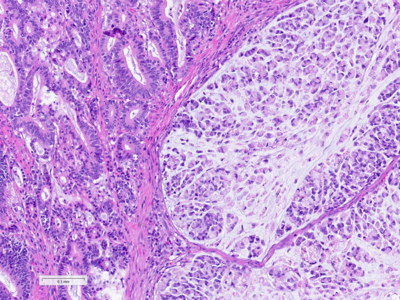

Histologically, the tumour was confirmed to be an adenocarcinoma invading through the gastric submucosa into the muscularis propria (Panel A), showing multiple architectural patterns. While the majority of the lesion displayed a tubular and papillary arrangement of neoplastic cells (Panel B), there were also mucin pools containing floating tumour cells (Panel C), as well as areas of discohesive signet-ring cells (Panel D), so called for their intracytoplasmic mucin droplet that eccentrically displaces the nucleus. The different architectural patterns were not entirely independent of each other nor were they intermingled, but rather arranged side by side (Panel E).

While gastric adenocarcinomas may exhibit intratumoral architectural heterogeneity, a lesion that displays a mixture of different histological subtypes and one of them is a signet-ring cell/poorly cohesive carcinoma is classified as a mixed carcinoma, mixed adenocarcinoma or mixed-type carcinoma/adenocarcinoma.